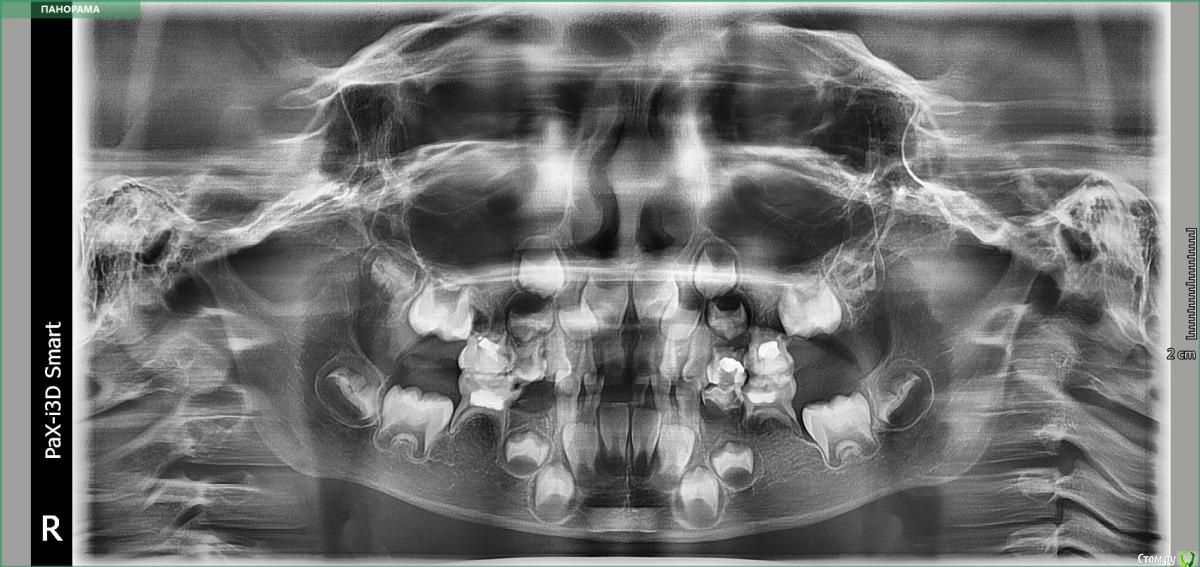

hoggard22 Опубликовано 12 сентября, 2019 Поделиться Опубликовано 12 сентября, 2019 Здравствуйте.Может кто-нибудь знает. У ребенка 5 лет на верхней 4-ке нашли свищ. Вскрыли пломбу, полоскали с содой, но через 3 недели воспаление не ушло, зуб подвижен, хотя ребенок не жалуется. Корень у зуба начал рассасываться. Но когда сделали снимок заметили, что под 5-ой нет постоянного зуба. Сделали панорамный снимок. По нему вроде как не видно 5-ку, возможно она есть. Встал вопрос удалять ли 4-ый зуб. Мнения разошлись. Одни стоматологи говорят, что нужно удалять, что бы не было гипоплазии постоянных зубов. Другие говорят, что удалять рано и в практике не встречали такого, что свищ может оказать влияние на постоянный зуб. Все таки как лучше поступить, что бы сформировать красивые постоянные зубы ? Ссылка на комментарий